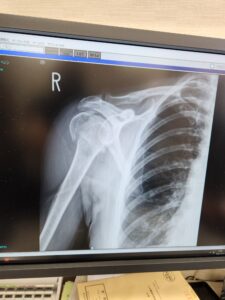

A photo of me broken. They did a bone density scan while in hospital, and found my bones were in good order – so, I managed to break myself by throwing myself really hard onto the ground…

Ouch!